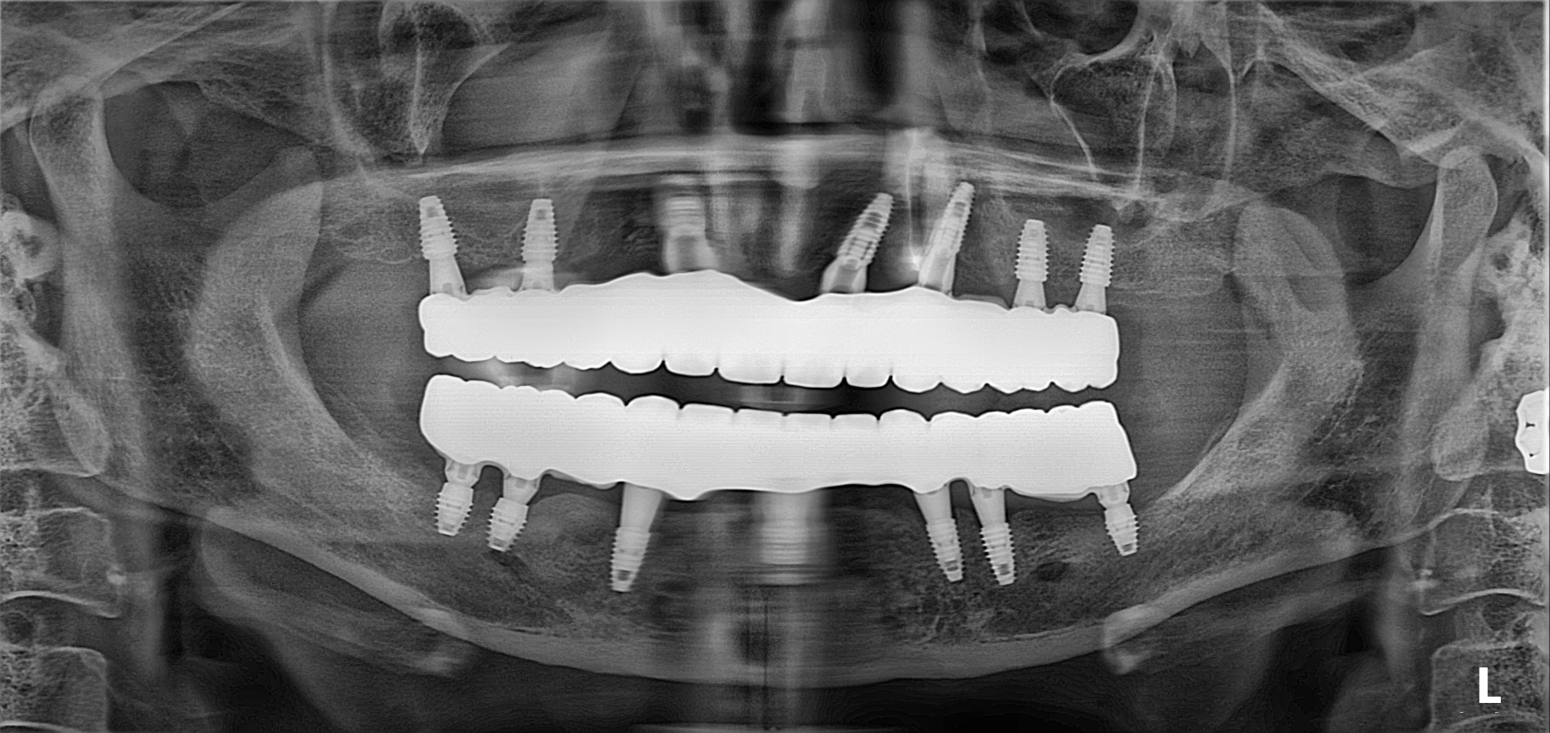

1. Surgical Phase (All-on-6): Six dental implants were strategically placed in both the maxillary and mandibular arches. This "All-on-6" configuration provides a robust foundation, allowing for a fixed bridge that mimics the function and feel of natural teeth.

4. Final Delivery: Precision-milled, full-arch zirconia bridges were delivered. These restorations provide the strength necessary for a full range of mastication while offering a highly aesthetic, natural-looking result that remains securely in place.